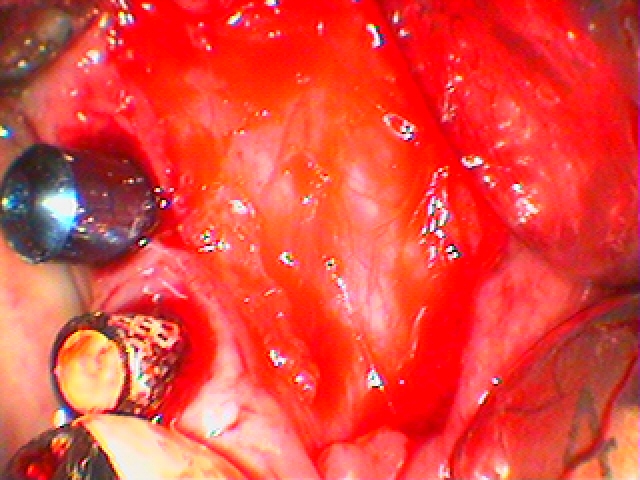

歯肉移植。| |広島市安佐南区の歯科医院 歯肉移植。 トップ お知らせ・ブログ 歯肉移植。 歯肉移植。 Web診療予約 初めての方へ 選ばれ続ける理由 院内設備について 歯が痛いしみる一般歯科 歯がぐらぐらする歯周病 健康な歯を保ちたい予防歯科 子供の虫歯予防をしたい小児歯科 銀歯をセラミックに審美歯科 白い歯を目指しませんか?ホワイトニング 矯正専門医がいるので安心矯正歯科 抜けた歯を補いたいインプラント・入れ歯 医院案内 スタッフ紹介 メリィハウス歯科クリニックオフィシャルホームページ ラベンダー歯科クリニックオフィシャルホームページ お知らせ・ブログ ホーム 診療科目 一般歯科 歯周病治療 予防治療 小児歯科 審美治療 ホワイトニング 矯正歯科 入れ歯・インプラント マウスピース矯正 初めての方へ 院長・スタッフ 設備紹介 医院案内・アクセス メニューを閉じる